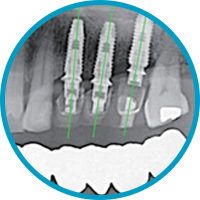

시술 전 보철물의 형태와 임플란트가 식립 될 위치를 파악하여, 골 고직 및 신경위치를 확인하여 임플란트 시술 계획을 수립 합니다.

시술 전 시술에 대한 정보의 부족으로 치료와 신뢰를 할 수 있는지에 대한 고민이 있었 습니다. 3D 컴퓨터 모의시술은 수술 유도장치로 미리 식립 될 위치를 파악하기 때문에 신뢰 할 수 있는 장점을 가지고 있습니다.

제작 된 맞춤형 수술 유도장치를 이용하여 위치와 각도로 임플란트가 식립이 되며, 인접 치아와 균형과 교합을 고려한 최종 보철물이 장착 됩니다.

출현, 통증, 붓기를 동반한 감염 위험이 높은 절개시술과 임플란트가 잘못 식립될 경우 신경 손상, 보철물의 파손의 가능성이 높습니다. 맞춤형 임플란트 시술은 비절개 시술로 회복이 빠르고 감염 위험이 낮으며, 수술 유도장치를 통해 모의시술대로 진행 하기 때문에 시술에 대한 오차가 적은 장점을 가지고 있습니다.